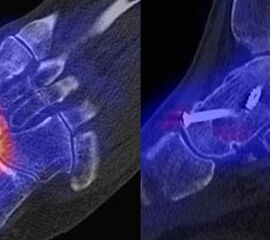

Beispiele für SPECT/CT-Untersuchungen nach OSG-TEP sind in den Abbildungen 6.1. bis 6.3. abgebildet.

Weltweit nimmt die Prävalenz von Sprunggelenk-Prothesen durch Verbesserungen der Implantate und chirurgischen Techniken zu. Trotzdem berichtet ein signifikanter Anteil von Patienten über persistierende Beschwerden nach Prothesen-Implantation, sodass in der Literatur über Revisionsraten in bis zu 39 % der Fälle berichtet wird 5051. Die Ermittlung der Schmerzquelle mit den konventionellen bildgebenden Verfahren (Röntgen, CT, MRT (auch mit Metall-Artefakt-Reduktion)) ist begrenzt, so dass hier die SPECT/CT die Aussagekraft ähnlich wie bei der Beurteilung anderer Prothesen (z. B. Knie und Hüfte) signifikant erhöht. Verschiedenste Fragestellungen müssen bei der Evaluation einer schmerzhaften Sprunggelenk-Prothese beantwortet werden: Achsenstellung, Prothesenlage, Impingement, Lockerung, Senkung von Prothesenkomponenten, Frakturen, Zysten, Osteolysen, Anschlussarthrosen, Infektionen, Nervenschäden, CRPS, Materialunverträglichkeiten.

Zur Zuordnung von Mehrspeicherungen und morphologischen Veränderungen im Bereich von Prothesen eignen sich folgende Kriterien 51:

• Flächiger starker Fokus am Prothesen-Knochen-Interface → V. a. Lockerung

• Fokus medial oder lateral am Prothesen-Knochen-Interface → V. a. fokaler biomechanischer Stress aufgrund von Fehlstellung der Prothese oder des Rückfußes

• Fokus medial oder lateral im Gelenkabschnitt / Zone zwischen Talus und den Malleolen → Ausdruck eines Impingement

• Im CT zart randsklerosierte rundliche Osteolyse(n) am Prothesen-Knochen-Interface mit metabolischem Fokus → V. a. symptomatische Zyste

• Fokale oder flächige Mehranreicherungen in angrenzenden Gelenken in Verbindung mit arthrotischen Veränderungen im CT → V. a. symptomatische Arthrose